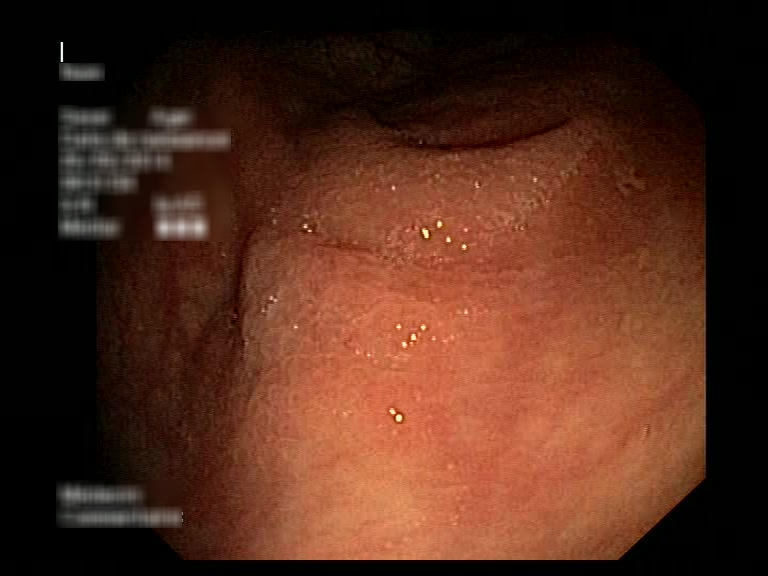

| Lesion | White Light Frame | NBI Frame | White Light Video | NBI Video | Camera Calibration |

| hyperplasic_01 |  |

|

WL.mp4 | NBI.mp4 | cam.xml |